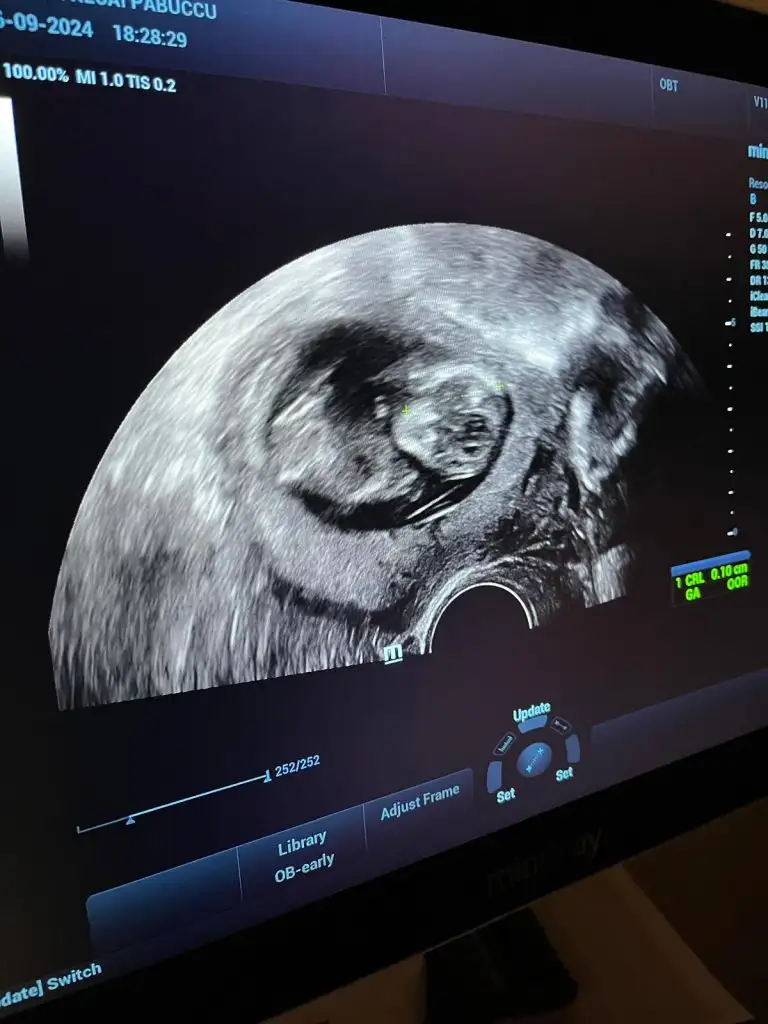

Kimse yok mu12 haftalik karindan ultrason rica etsem cinsiyet tahmini yapabilir misiniz

Başka foto yok mi12 haftalik karindan ultrason rica etsem cinsiyet tahmini yapabilir misiniz

Bacak arası fotosu bu doktor kız diyor ama ben hala erkek hissediyorummmCanım hiç belli olmuyor bacak kısımları anlayamayuz böyle

Evet doktor kız dedi ama ben ısrarla erkek hissediyorummm 14. Haftada söylediBence kız bir an öyle hissettim nedenini bilmeden ama tabi ne olursa olsun sağlıklı olsun

Evet doktor kız dedi ama ben ısrarla erkek hissediyorummm 14. Haftada söyledi

Bacak arasını boş gördüğü için demiştir kızda yanılma payı var detaylı ultrasona girene kadar bende erkek hissediyorum ama daha belli değil 15 hafta 2 günlük benim bebişim deEvet doktor kız dedi ama ben ısrarla erkek hissediyorummm 14. Haftada söyledi